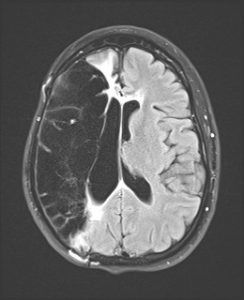

A brain scan showed that the stroke had affected two-thirds of Amy’s right hemisphere, said Amy’s neurologist, Dr. Sharon Poisson, medical co-director of the certified Comprehensive Stroke Center and an associate professor of neurology at the University of Colorado School of Medicine.

The extensive damage caused Amy’s brain to swell significantly, so doctors performed a hemicraniectomy. With a section of her skull removed, her brain swelling didn’t put fatal pressure on other areas of her brain. (Doctors later reattach the skull once swelling recedes, which in Amy’s case was several months later.)